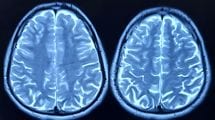

素人目でも脳の形が完全に変わった…認知症でも脳梗塞でもない不治の病の60代夫を支える薬剤師妻の深い愛情

並んで歩いていると急に姿が消え、地面に転がっていた素人目でも脳の形が完全に変わった…認知症でも脳梗塞でもない不治の病の60代夫を支える薬剤師妻の深い愛情